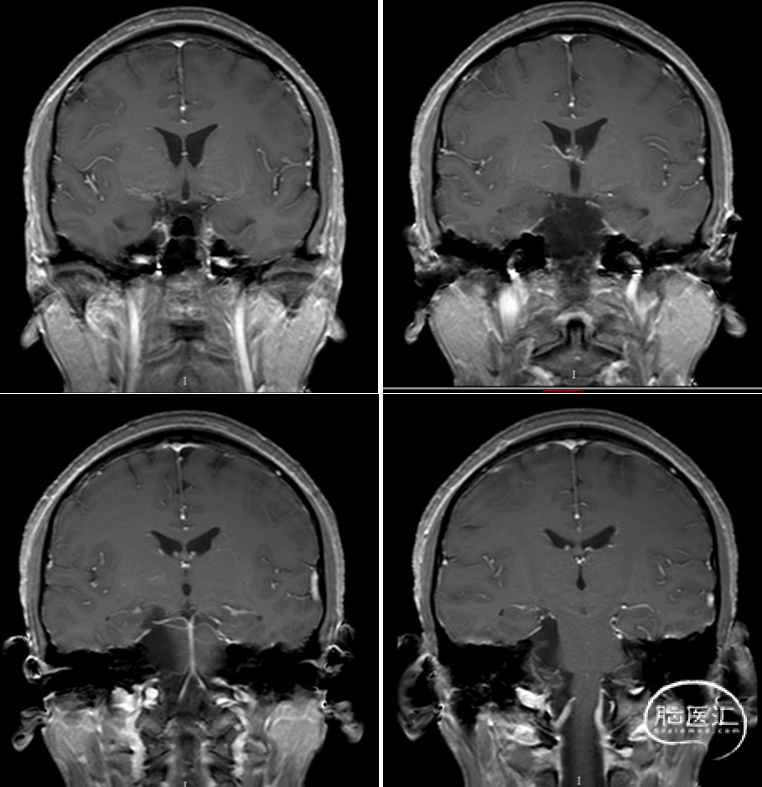

术后MRI